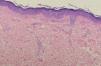

En el estudio histopatológico de una lesión del tronco se observaba una hiperqueratosis con ligera paraqueratosis. En una epidermis ligeramente acantósica el cuerpo espinoso estaba desorganizado con disqueratosis, mitosis y células de diferente tamaño dando un aspecto bowenoide. También existían, en la capa granulosa y la parte alta de la espinosa, células de citoplasma pálido y halo claro perinuclear característico de las verrugas planas (figs. 2 y 3).

Las manifestaciones clínicas e histopatológicas de la EV adquirida son semejantes a las de la EV clásica. El hallazgo histopatológico característico consiste en una hiperqueratosis leve o moderada y acantosis a expensas de células de citoplasma amplio, pálido y basófilo con ocasionales halos claros perinucleares. Este patrón típico es infrecuente y se encontró sólo en 3 de 18 pacientes con EV clásica y en 8 de 19 pacientes con EV adquirida9,10. En los demás casos el estudio histopatológico mostró engrosamiento y desorganización de la capa granulosa y la presencia aislada de células con halo claro perinuclear9,10. En el estudio histopatológico de nuestro caso alternaban o coexistían, en distintas zonas, imágenes tipo verruga plana y áreas semejando la enfermedad de Bowen.